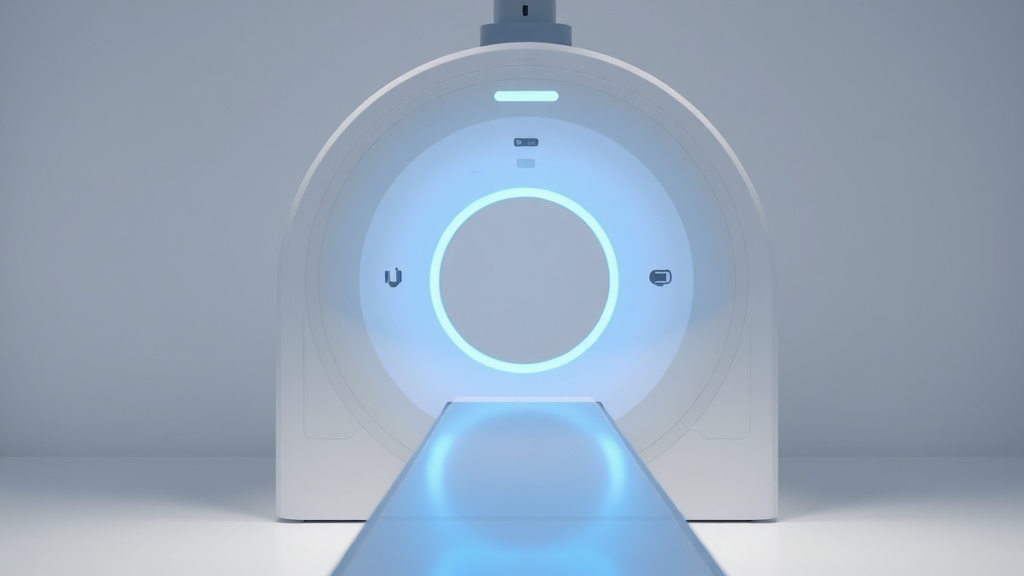

The Papillon treatment involves inserting an X-ray tube through the anus to deliver precise radiation doses directly to cancerous tumours. It is specifically recommended for patients with rectal tumours measuring 3cm or smaller, or those who choose to avoid surgery due to high risk. Pioneers of the technique, like Professor Sun Myint, have been using it for over three decades, with trials demonstrating remarkable success in preserving organs.